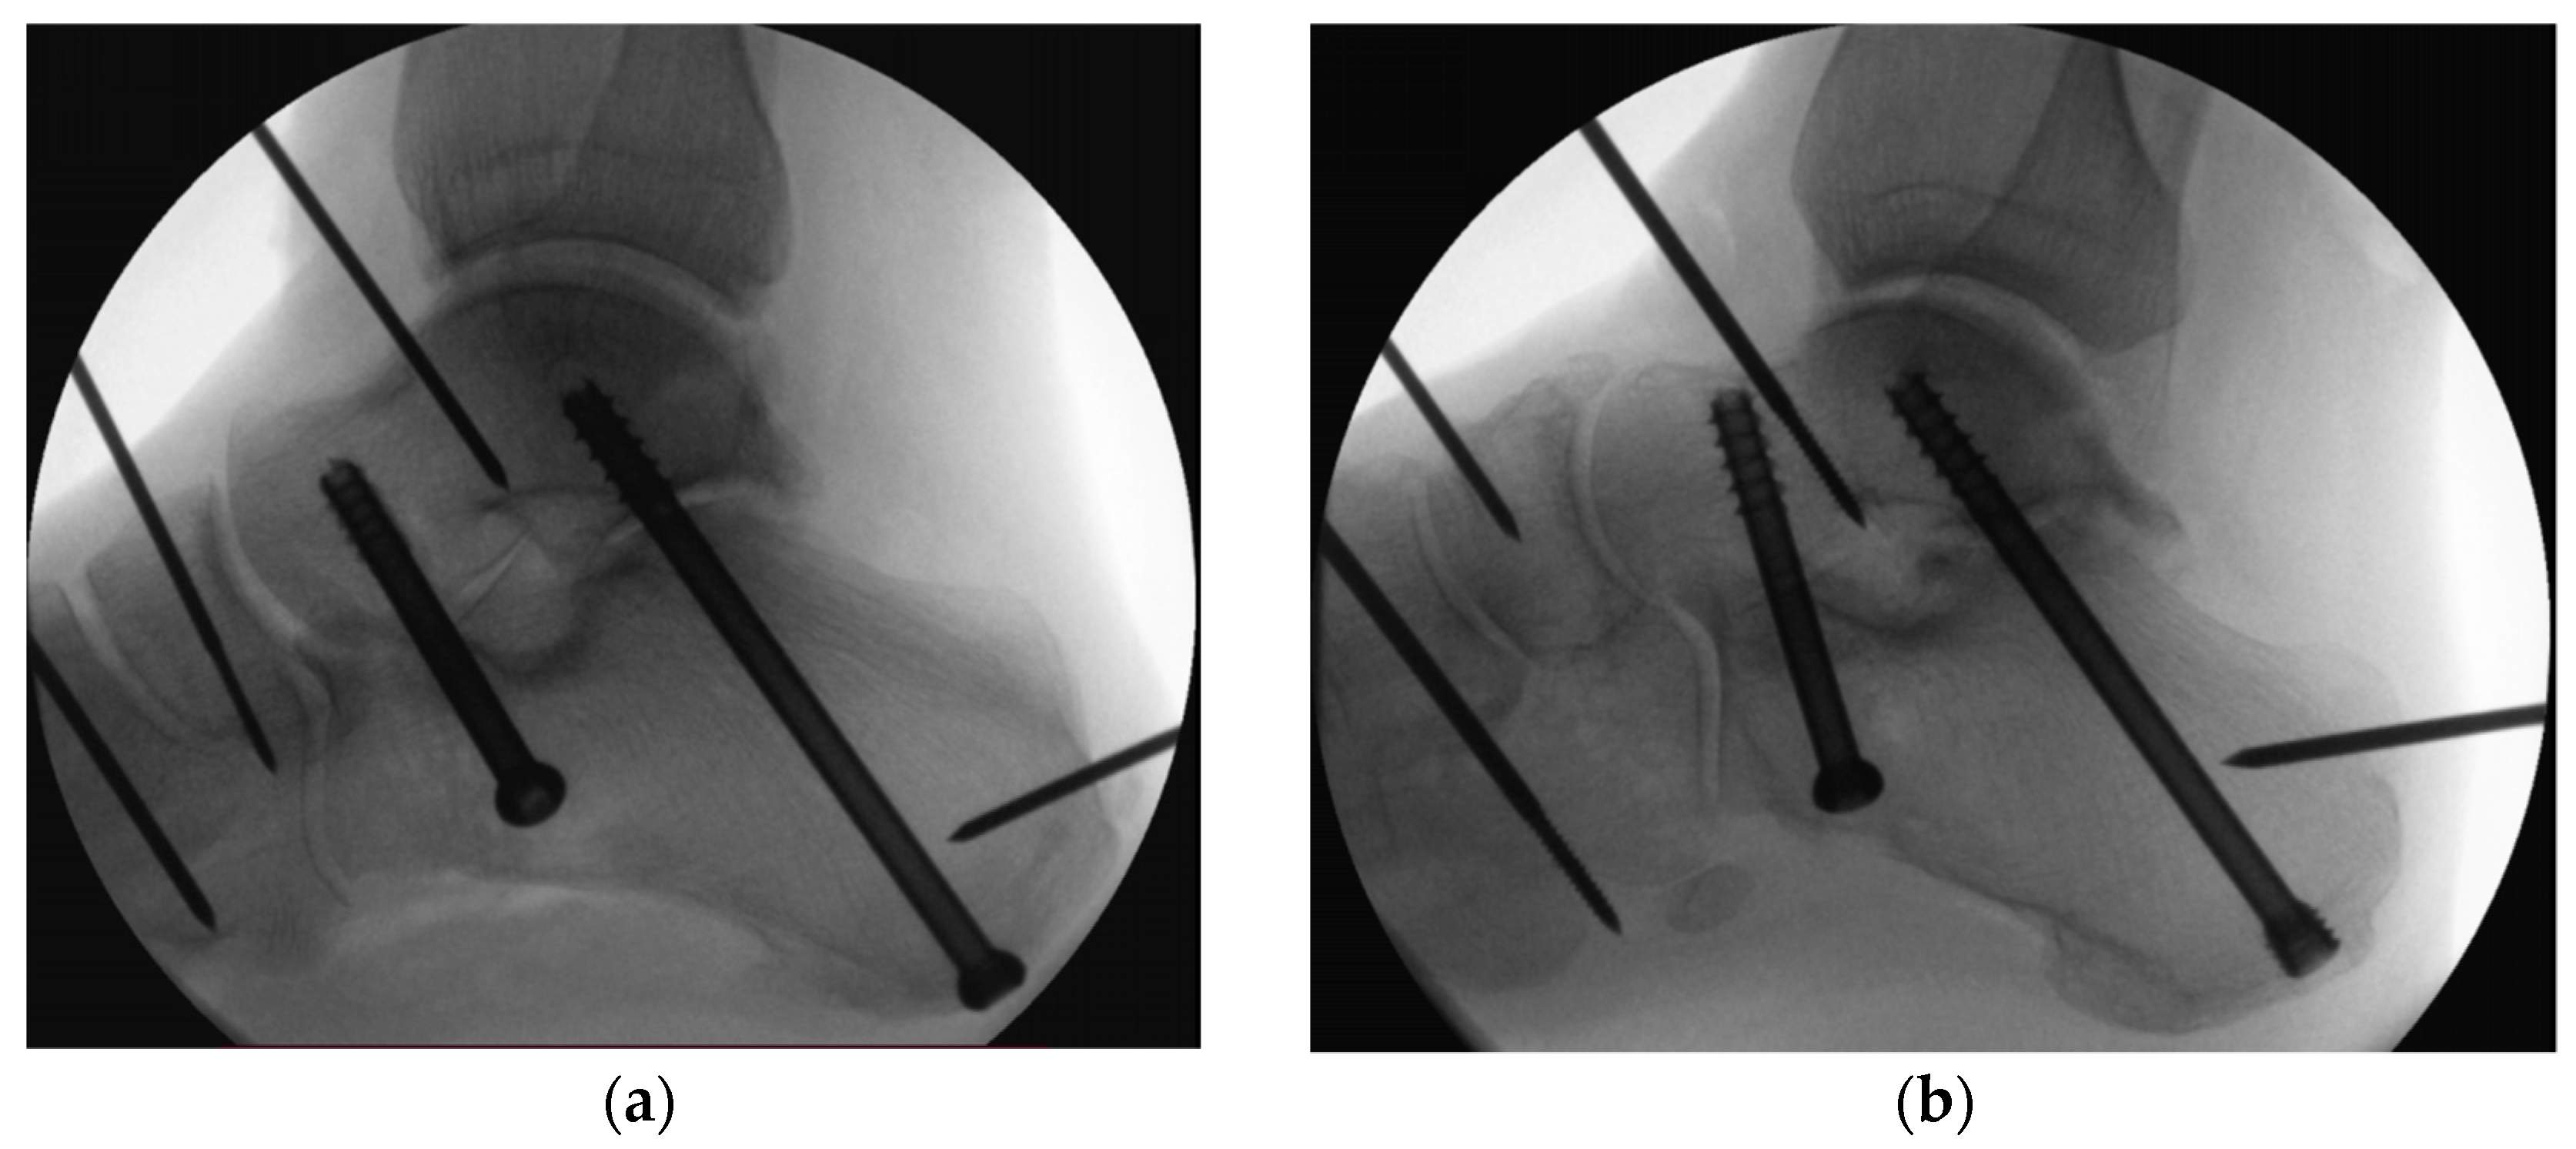

The specimens were assigned pairwise to two groups for SJA using either two 6.5 mm partially-threaded CCS (Group 1) of 16 mm thread length (DePuy Synthes, Zuchwil, Switzerland) or one posterior partially-threaded 6.5 mm CCHS and one anterior partially-threaded 6.5 mm CCS (Group 2), both of 16 mm thread length (DePuy Synthes, Zuchwil, Switzerland) (Figure 5).

Figure 5.

Radiographs visualizing the screw positions for delta-configuration subtalar joint arthrodesis using either two cannulated compression screws in Group 1 (a) or one posterior cannulated compression headless screw and one anterior cannulated compression screw in Group 2 (b).